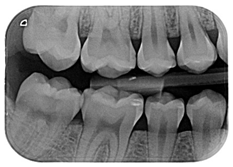

| 3 | A 29-year-old patient visits the dental clinic to evaluate his/her general oral state. A complete clinical examination is carried out and no pathological signs were observed. Bitewing x-rays are performed, and various radiolucent lesions limited to the enamel were observed on the right bitewing x-ray. | ![]() | Select the most adequate treatment alternative for tooth 4.6 from the answers provided. |

| [13,14] | |